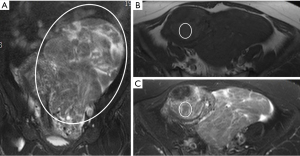

A 52-year-old postmenopausal female patient presented to our hospital with a six-month history of lower abdominal discomfort and distension. During the physical examination, a 20 cm hard mass with poor mobility was palpated in the pelvic cavity, with no tenderness. The patient has no history of digestive or cardiovascular diseases, and no family history or genetic history. Hormonal examination revealed elevated prolactin levels at 30.67 µg/L (normal range: 2.74–19.6 µg/L). Subsequent transvaginal ultrasound examination revealed an irregularly shaped, well-defined, hyperechoic mass measuring 169 mm × 77 mm in the pelvic cavity, with unclear demarcation from the uterus. Multiple slightly hyperechoic nodules of varying sizes were observed inside (Figure 1A), suggesting a pelvic solid mass with undetermined nature. Abdominal ultrasound further indicated an irregularly shaped hyperechoic mass measuring approximately 46 mm × 17 mm within the posterior segment of the hepatic end of the IVC, suggestive of an intraluminal mass (Figure 1B). Given the presence of an intraluminal mass in the IVC, further investigations were performed, including contrast-enhanced computed tomography (CT) of the upper abdomen and pelvic magnetic resonance imaging (MRI). CT scan showed a long, strip-like, mixed low-density lesion within the IVC, containing fat density signals (Figure 2A); contrast-enhanced CT transverse section (Figure 2B,2C) and coronal section (Figure 2D,2E) revealed a filling defect in the IVC with visualization of a long, thin, enhancing vessel. Additionally, a filling defect was observed in the pelvic vein extending upward to the left renal vein, subsequently joining the IVC (Figure 2F-2I). On T2-weighted image with fat-suppression (T2FS) MR Images, irregular mixed signal masses were found in the pelvic cavity (Figure 3A). Some areas containing adipose tissue showed high signal intensity on T1W images (Figure 3B), but this area was suppressed as low signal on the T1W image with fat-suppression (T1FS) (Figure 3C). Based on the aforementioned imaging findings, the diagnosis of IVL involving the pelvic veins and IVC was considered.

The clinical symptoms of this disease are atypical, but its characteristic imaging findings can help with diagnosis. Due to the presence of fat components, ultrasound shows higher echogenicity (while venous leiomyomas generally show lower echogenicity), similar to renal angiomyolipomas. In this case, transvaginal ultrasound of the uterus revealed nodules of varying sizes with slightly higher echogenicity, which were actually leiomyomas containing adipose tissue (as leiomyomas typically show low echogenicity). Abdominal ultrasound showed a high echogenic mass within the IVC, which was also due to the presence of adipose tissue within the tumor, resulting in high echogenicity (as thrombi usually show low or moderate echogenicity). CT and MRI findings of fat and vascular tissue are also important diagnostic tools. The contrast-enhanced CT scan revealed a large filling defect within the IVC, containing low-density fatty components. Post-contrast imaging did not show significant enhancement of the fatty component, but a slender small vessel within it demonstrated marked enhancement. MRI showed that the soft tissue mass had high signal intensity on T1W images and was completely suppressed on T1FS images, further indicating that the mass was not just a leiomyoma but a lipoma-like liposarcoma containing fat tissue. Additionally, a filling defect in the pelvic vein extending upward to the left renal vein and draining into the IVC was identified. Intraoperatively, the uterus was found to be normal in size and morphology, with the mass located at the broad ligament of the uterus. From this, we infer that the primary site of the lesion is located in the broad ligament of the uterus within the pelvic cavity, then it spreads through the pelvic vein and extends into the IVC. Based on these imaging findings, which revealed the presence of fat and vascular tissue within the mass, along with the involvement of the pelvic and IVC veins, the diagnosis of LPL is considered appropriate. It is crucial to differentiate how filling defects in the IVC are not misdiagnosed as poor opacification of contrast agent during enhancement. If there is contrast agent filling in the distal part of the lesion but not in the proximal part, then we can confirm the presence of an occupying lesion in the IVC causing the filling defect rather than incomplete opacification of the contrast agent. Additionally, when the left renal vein joins the IVC, turbulence is created that may appear as a filling defect. How can we distinguish between turbulence and a defect caused by an occupying lesion? Turbulence-induced defects are generally irregular in shape and only present at the entrance of the turbulence, while defects caused by an occupying lesion have clear boundaries and are present throughout the section of the occupying lesion, requiring careful observation for differentiation.